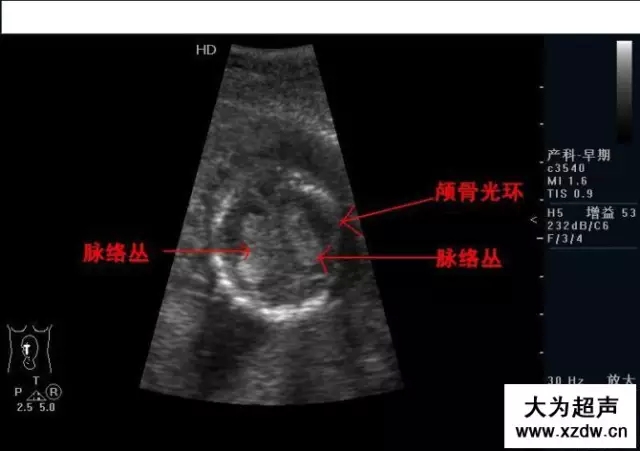

產(chǎn)科超聲正常圖片